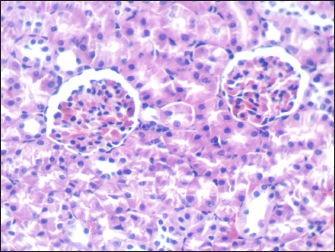

Mouse liver from the control group shows a normal radiant arrangement of the hepatic cells (Fig. 1). Pathological changes in treated liver sections showed an increase in the immune cells’ infiltration, and marked congestion were observed in almost all mice. In group 1, there was hemorrhage, congestion, and degenerated cells (Fig. 2). In group 2, there was congestion of the central vein, infiltration of immune cells, and degeneration of hepatocytes (Fig. 3). Whereas in group 3, the previously mentioned changes were markedly intensified with severe hemorrhage and marked sinusoidal dilatation (Fig. 4). Mouse kidney of control group shows normal cellular appearance (Fig. 5); however, pathological changes in treated kidneys sections reveals congestion, tubular necrosis and cast in some tubule’s lumen, group 1 (Fig. 6). In group 2, there was congestion, tubular necrosis, necrotic debrites in the tubuli lumen and cast (Fig. 7). Whereas in group 3 there was marked congestion, tubular and cellular necrosis, necrotic debrites in the tubular lumen and degenerated cells (Fig. 8).

Fig. 1. Section of mouse liver from control group showing normal radiant arrangement of the hepatic cells (H and E, 400×).

Fig. 5. Section of mouse kidney of control group shows normal cellular appearance (H and E, ×400).